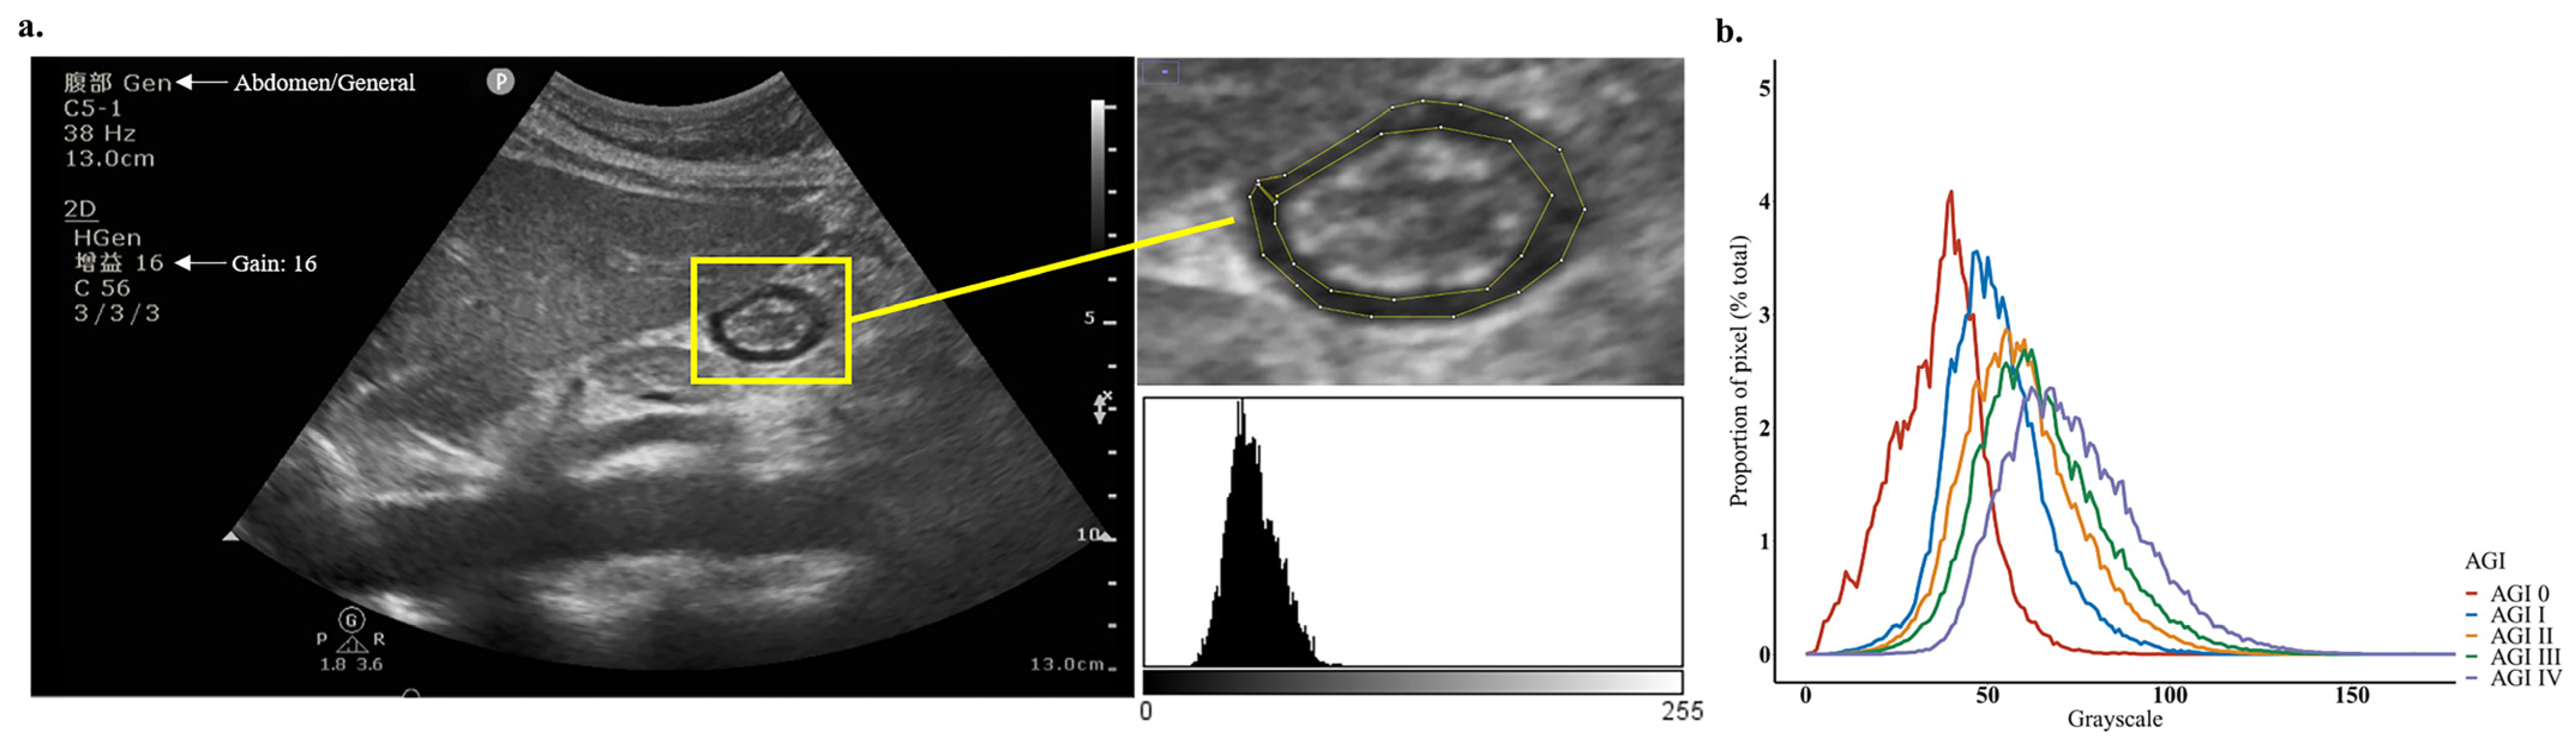

2.2. POCUS Examination and Echodensity Measurement

3.2. Measurement of Gastric Antrum Echodensity and Consistency Analysis

3.3. Association between Gastric Antrum Echodensity and AGI Grade